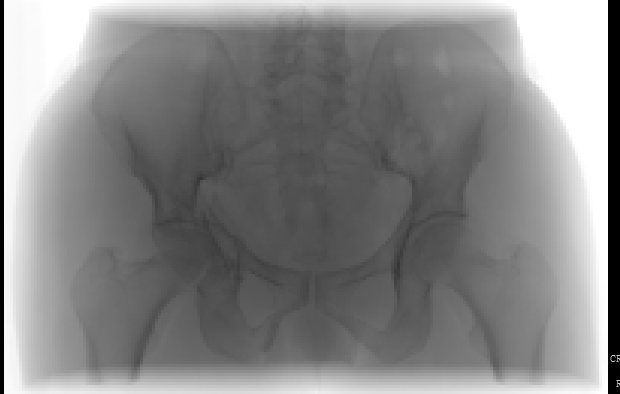

患者性別:男      年齡:50歲

診斷:右髖臼骨折

術(shù)前x線片